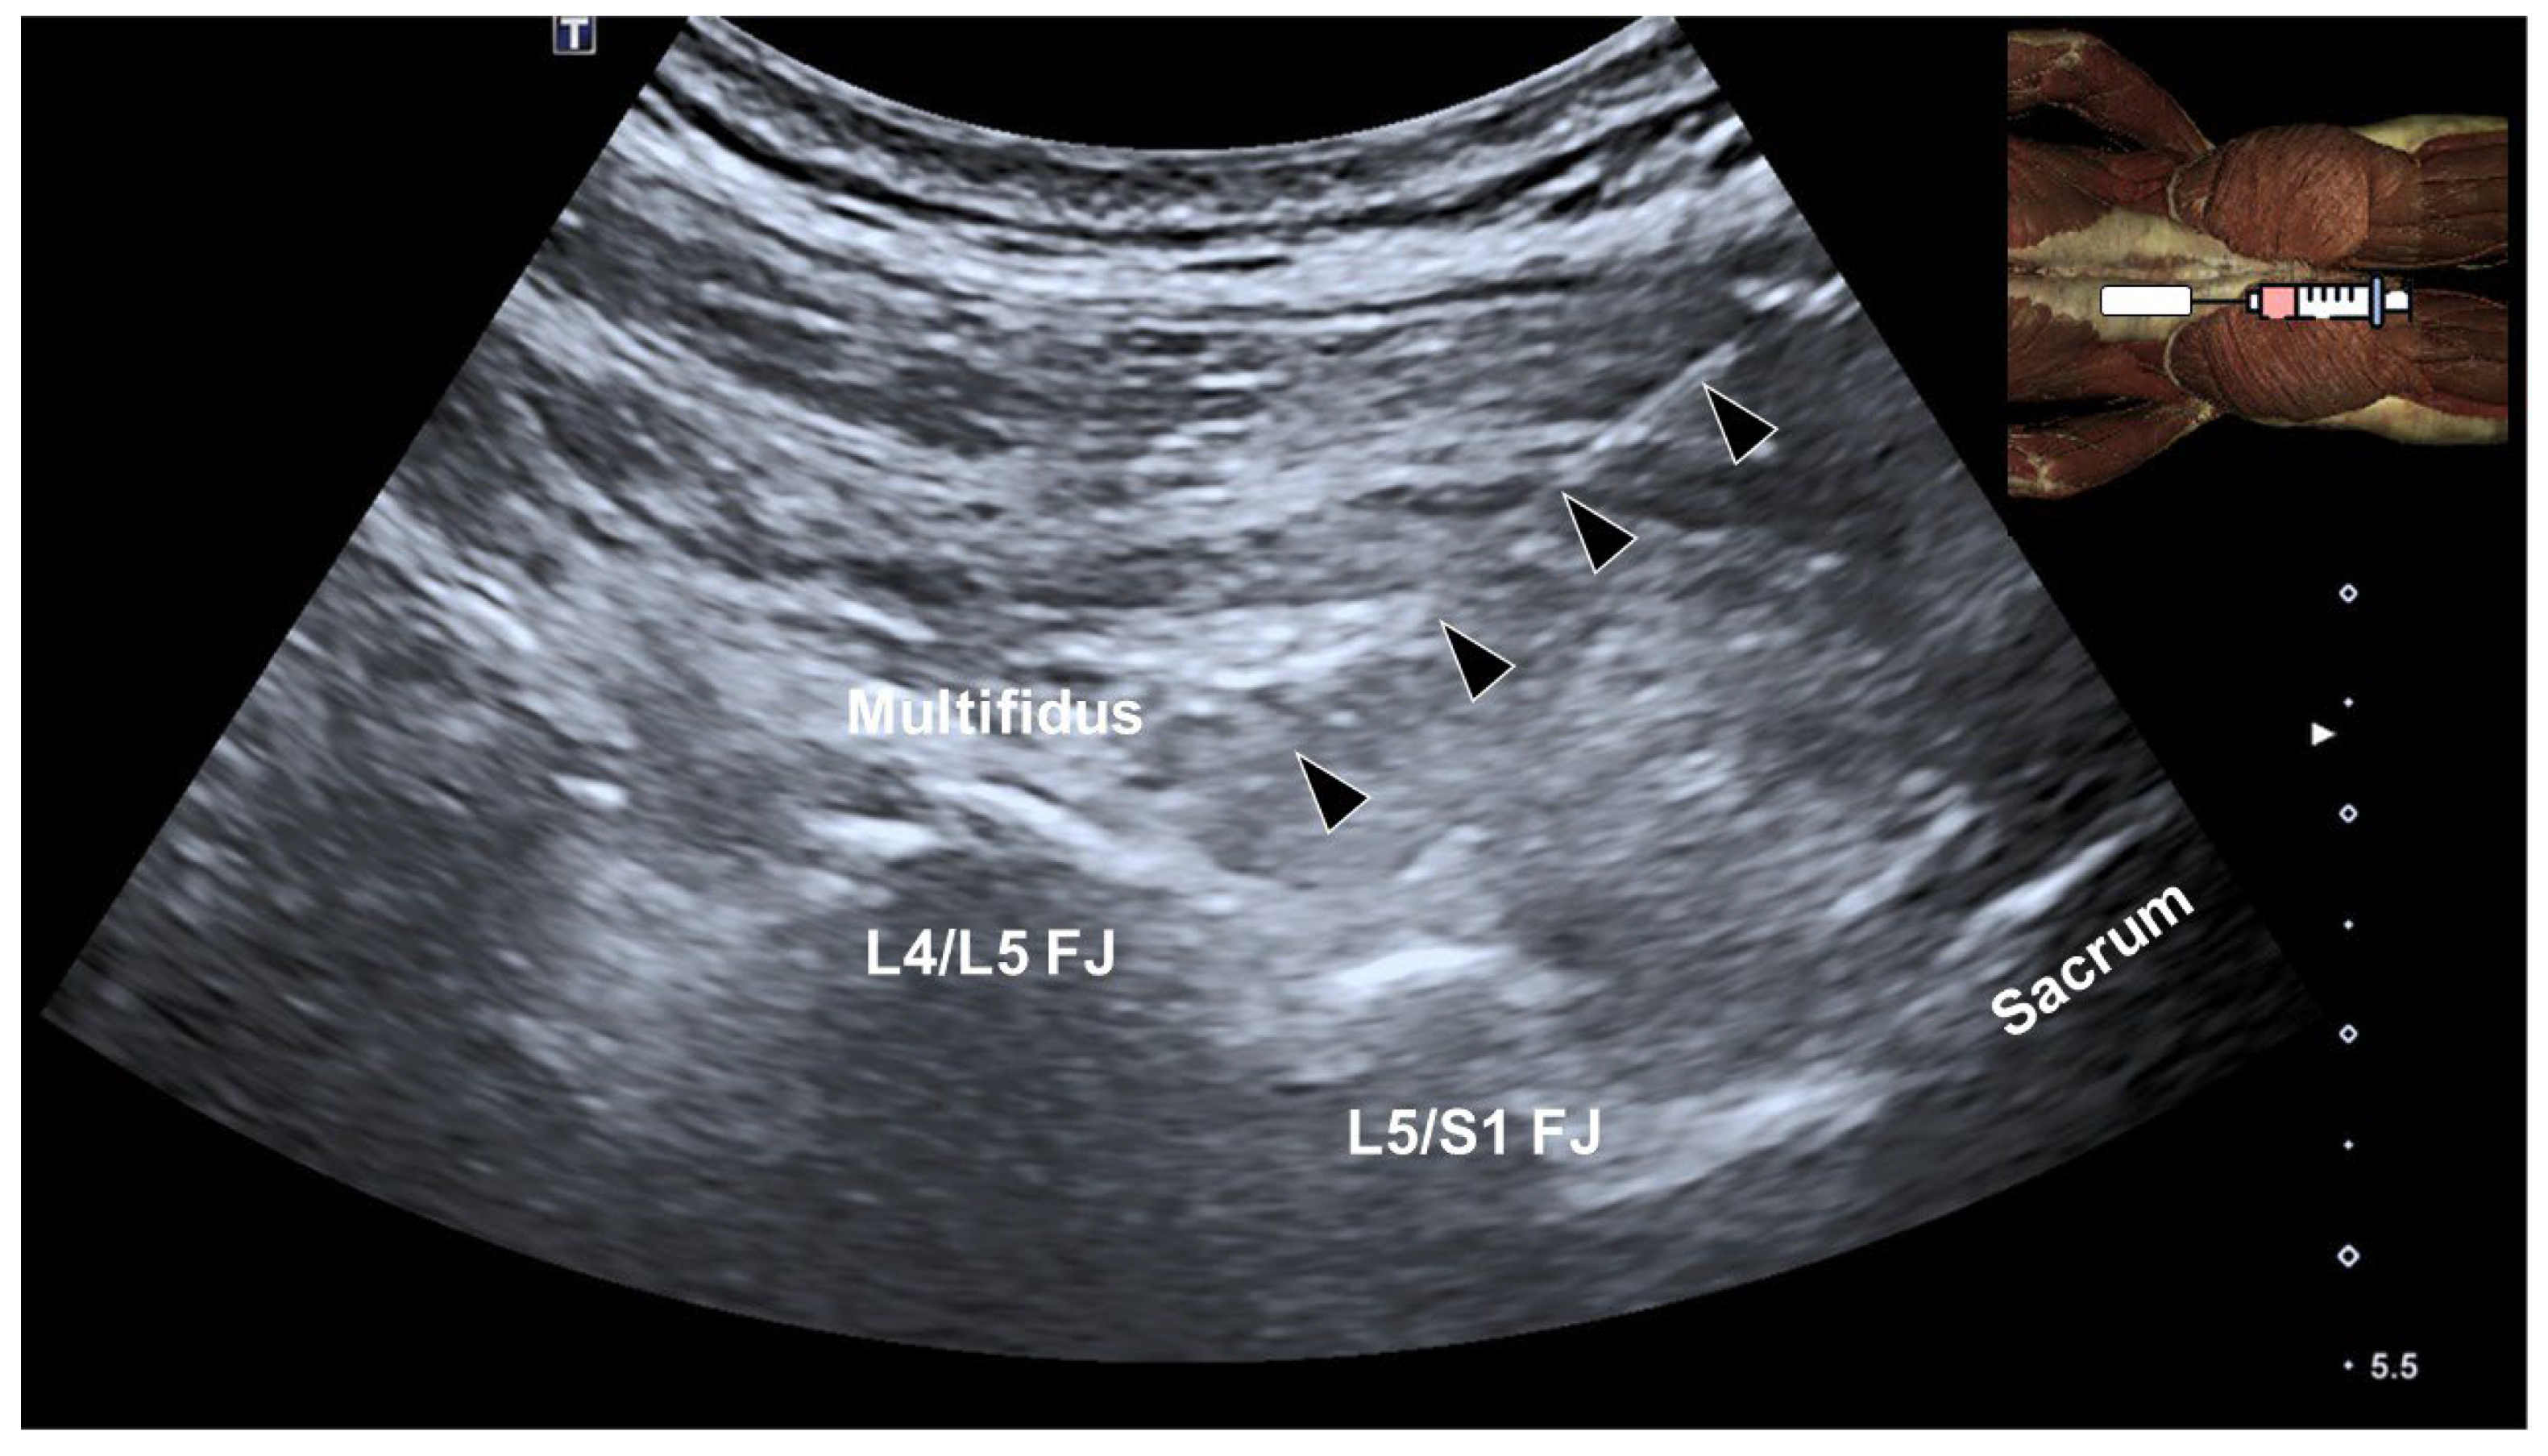

4. Multifidus Muscle and Low Back Pain

5. Ultrasound-Guided Injections Targeting the Multifidus Muscle

- Hung, C.Y.; Wang, B.; Chang, H.C.; Wu, W.T.; Liu, P.T.; Chang, K.V.; Su, D.C.; Mezian, K.; Ricci, V.; Özçakar, L. Pictorial Essay on Ultrasound and Magnetic Resonance Imaging of Paraspinal Muscles for Myofascial Pain Syndrome. Life 2024, 14, 499. [Google Scholar] [CrossRef]

- Suputtitada, A.; Chen, J.L.; Wu, C.K.; Peng, Y.N.; Yen, T.Y.; Chen, C.P.C. Determining the Most Suitable Ultrasound-Guided Injection Technique in Treating Lumbar Facet Joint Syndrome. Biomedicines 2023, 11, 3308. [Google Scholar] [CrossRef]

- Wu, W.T.; Chang, K.V.; Özçakar, L. Integrating Ultrasound-Guided Multifidus Injections with Repeated Peripheral Magnetic Stimulation for Low Back Pain: A Feasibility Study. J. Pain Res. 2024, 17, 2873–2880. [Google Scholar] [CrossRef]